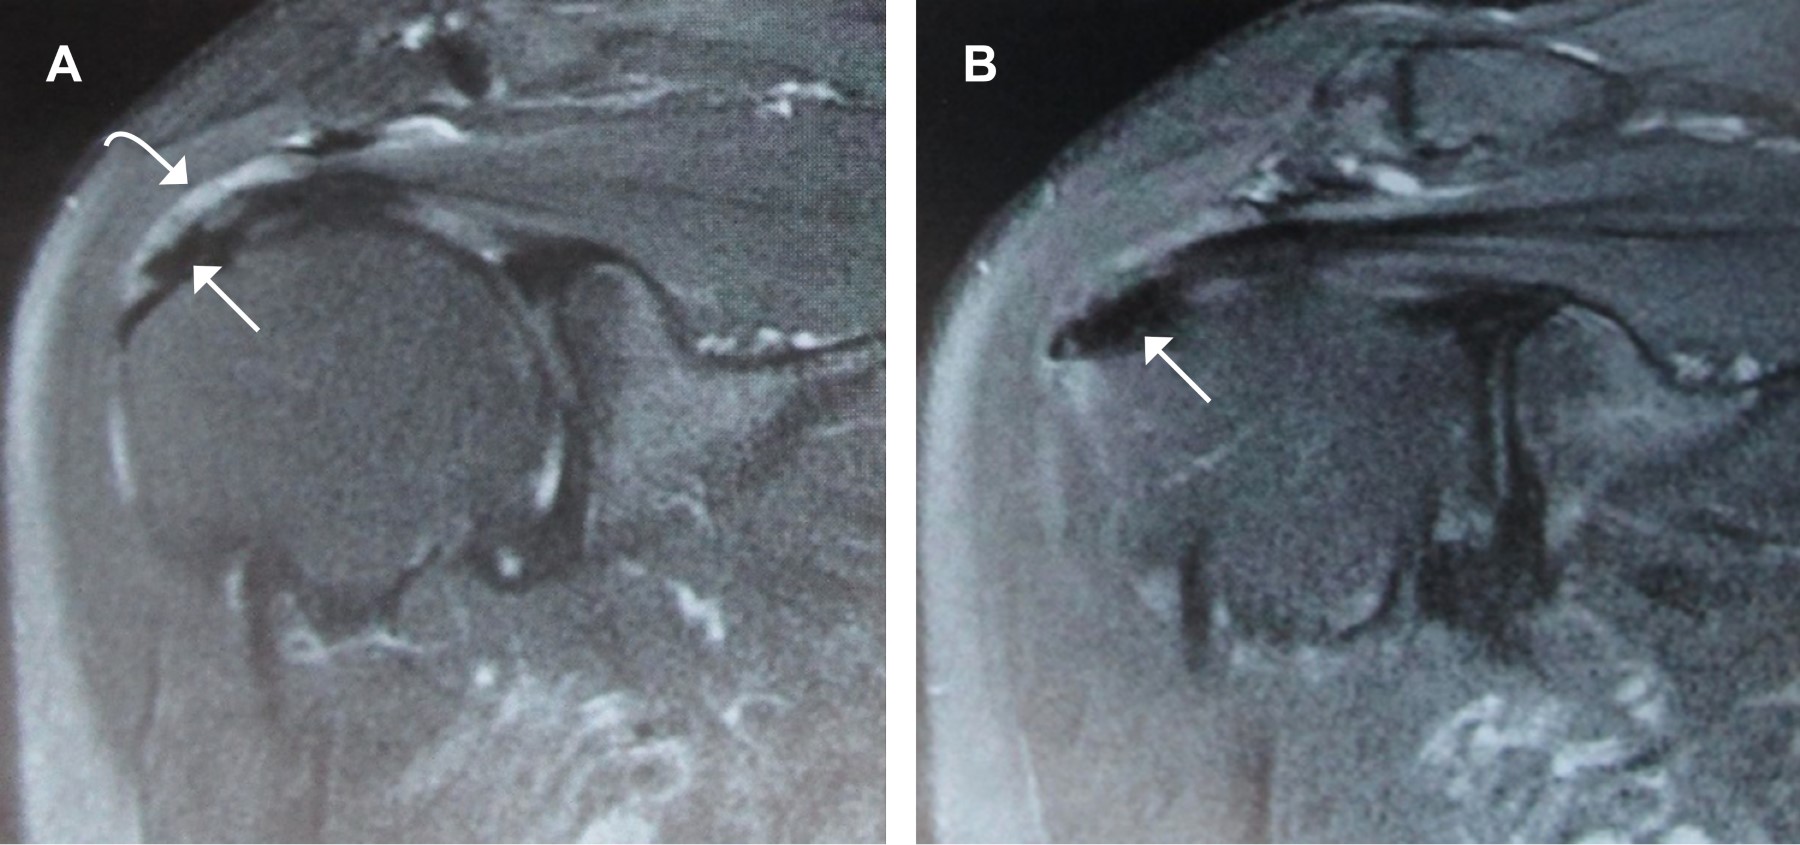

Los estudios por imágenes confirman el diagnóstico, incluso en casos asintomáticos, y se usan también para realizar el seguimiento. Las radiografías AP verdadera de hombro, lateral de escápula y outlet de hombro, son las utilizadas para determinar la extensión, localización y diseminación de la lesión del supraespinoso. Las radiografías AP en rotación externa permiten valorar al subescapular, mientras que la imagen AP en rotación interna detecta acumulación de calcio en el redondo menor e infraespinoso.16 El ultrasonido diagnóstico muestra mayor sensibilidad en detectar calcificaciones en el manguito, con la desventaja de ser dependiente del operador.17 La tomografía computarizada permite la localización más específica de los depósitos calcáreos, por otra parte el uso de la resonancia magnética es superior para determinar la existencia de otras lesiones y del estado del tendón18 (Figura 2).

Figura 2